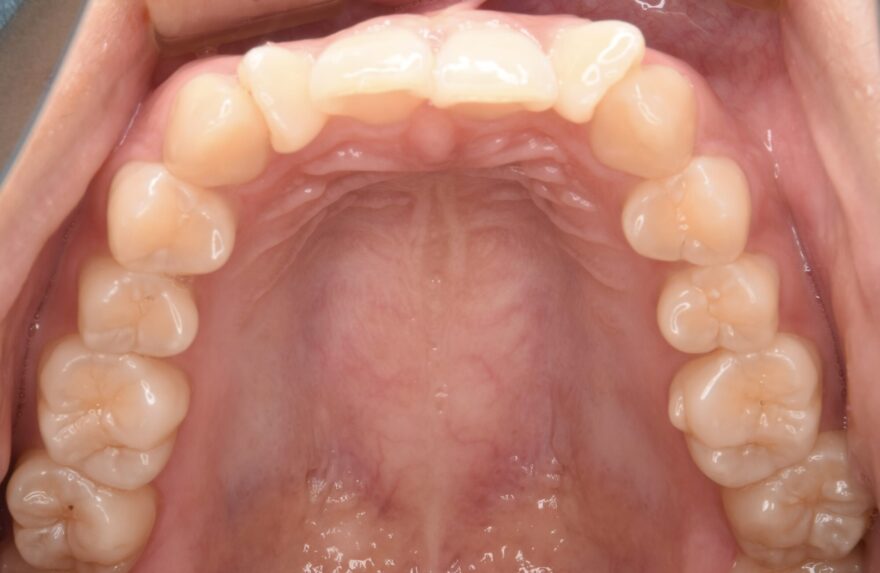

初診時の口腔内写真

前歯が捻じれてしまっています。

側方から見ると、前歯が90度以上回転していることがわかります。

最後方の奥歯が噛んでいません。